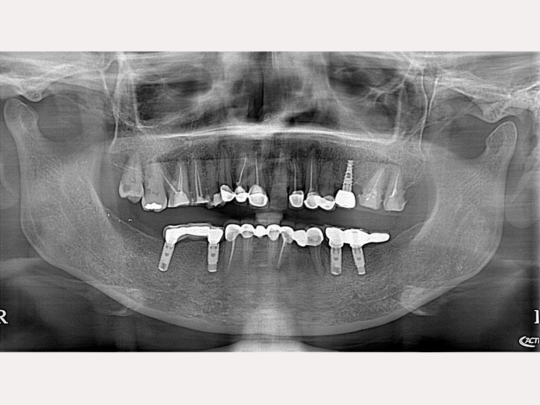

Implant

Before and After